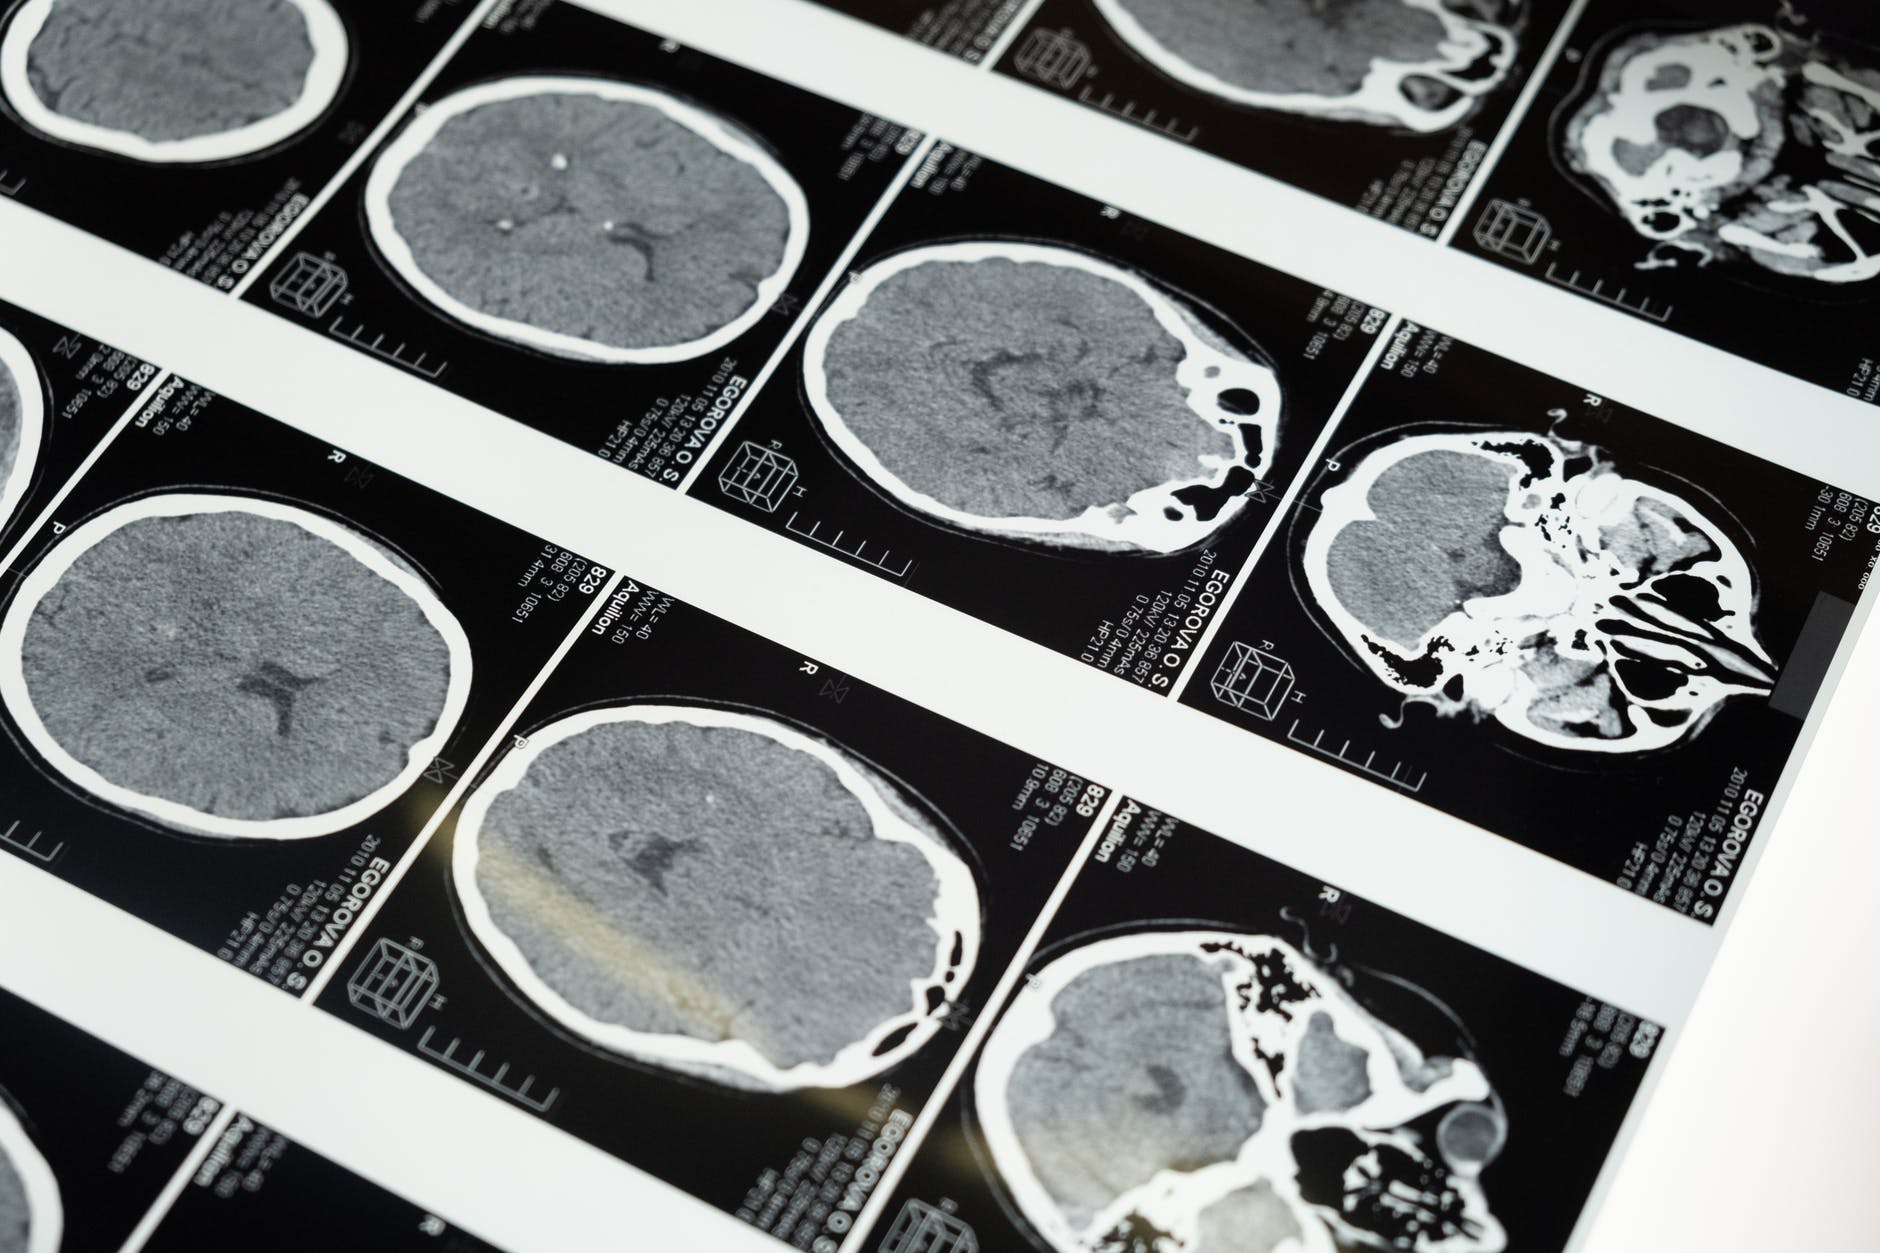

Möjligen behöver jag att du rekvirerar journaler och hjärnavbildningar, t.ex. CT-skalle, MR-hjärna osv, så att jag kan göra mig en bild av vad som har hänt dig.

I might need for you to request medical records and brain imaging, e.g. head/skull CT, MRI brain, etc., so I can get an idea of what has happened to you.